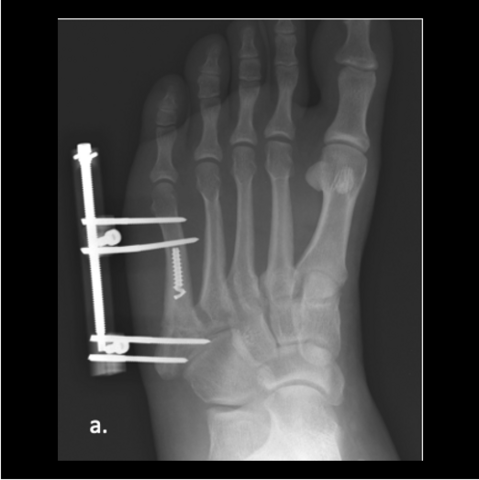

Figure 5a

Figure 5a. The 24-year-old required hardware removal and application of external fixation for gradual compression. Most cases heal within 6 weeks with gradual compression weekly.